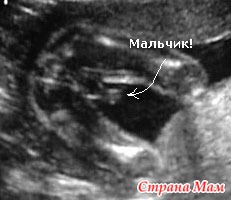

УЗИ-фотографии малышей в 22 недели: